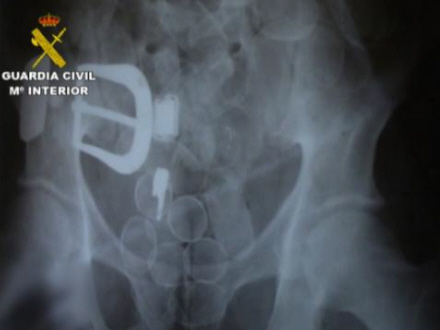

Ifølge rapporten fra Guardia Civil blev offeret, J.A.U.I., en colombiansk advokat med spansk pas, hyret af narkobagmanden fra sit hjemland til at transportere kokain i maven fra Sydamerika til Spanien.

Manden, der havde hårdt brug for penge, tog en lang rejse fra Colombia til Chile, hvor det angiveligt er lettere at slippe igennem kontrollen med narkotika. Herfra rejste J.A.U.I. videre til Spanien.

Lige efter ankomsten til Spanien fik manden forfærdelige mavesmerter og bad sin 'arbejdsgiver', den colombianske narkobagmand J.A.V.H, om at komme på sygehus. Alt tydede på, at der var gået hul på en af pakkerne i hans mave og at han hurtigt blev forgiftet indefra. Han havde akut brug for hjælp.

Men det afviste narkobossen, der var mere bange for at miste narkoen. Han gav i stedet sit muldyr en ordentlig dosis smertestillende medicin for at milde den ulidelige smerte.

Retsmedicinere har efterfølgende slået fast, at manden døde af forgiftning, og fik skåret maven op post mortem. Narkoen var herefter blevet taget ud, og maven var igen blevet syet sammen med fiskesnor.